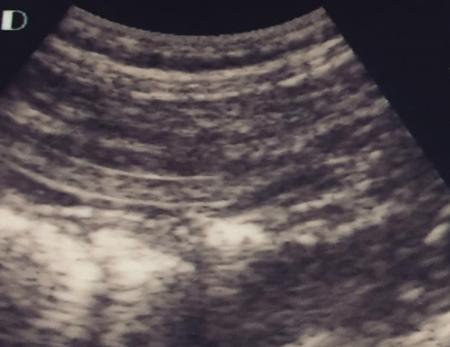

SMALL BOWEL IMAGING Poonam Narang, Himanshu Gupta The small bowel is a long tubular hollow abdominal viscus thrown into intricate folds and loops and packed into the abdominal cavity. It is approximately 5–7 m in length and extends from the gastric pylorus up to the ileo-caecal valve. It is anatomically divided into three parts: duodenum (meaning ‘in twelves’ as its length is roughly equal to the width of 12 fingers), jejunum (meaning ‘fasting’ as it was usually found empty after death) and ileum. The duodenum measures 20–25 cm in length and extends from gastric pylorus to the ligament of Trietz. It is a fixed ‘C’-shaped structure that cradles pancreatic head in its concavity. First part of the duodenum is a triangular conical structure with its base communicating with gastric antrum. Its apex points to the right and cranially, in close apposition with the gall bladder and the under surface of the liver. Second part of duodenum is almost vertical, lying in the right paravertebral gutter. The common bile duct courses obliquely posterior to it and drains at a papilla at its medial wall (the Ampula of Vater), after joining with the main pancreatic duct. Third part is horizontal, crossing the midline between the superior mesenteric artery (SMA) and aorta from right to left, caudal to pancreatic neck. Fourth part is again almost vertical, ascending left of the spine almost to the level of duodenal bulb and transitions to jejunum at duodenojejunal (DJ) flexure. Duodenum is mostly a retroperitoneal structure while the rest of the small bowel acquires a mesentery at the DJ flexure. The jejunum and ileum are intraperitoneal structures, suspended in the abdominal cavity from the posterior abdominal wall by the free end of their ‘fan-shaped’ mesentery and are thus relatively mobile. Though considered a part of small bowel, duodenum differs from the rest of the small bowel in structure as well as function. Plethora of the diseases that affect duodenum are distinct. Peptic ulcer disease affecting the first part does not affect the rest of the small bowel. Most other diseases affecting the duodenum arise from the surrounding structures like pancreas, gall bladder, bile duct, liver and the hepatic flexure of colon. Hence, on imaging, duodenal abnormalities should prompt a search for pathologies of the surrounding organs. While duodenum is structurally a distinct segment, the structural transition from jejunum to ileum is seamless, with no external demarcating point. Histologically, and also on imaging, all three segments have clear identities. Their mucosal lining, folds and presence of submucosal lymphoid follicles are allocated in accordance with their specific functions. Jejunal loops occupy left hemiabdomen and ileal loops, with ileo-caecal junction, lie in the right lower abdomen. Jejunum is about two-fifths of the length of the small bowel, and the ilium forms the rest of the three-fifths of the entire 5–7 m. ‘Terminal ileum’ is a term arbitrarily but commonly used in clinical practice to denote the portion of ileum just proximal to ileo-caecal junction harbouring abundant lymphoid tissue in its walls and playing host to a number of pathologies. At ileo-caecal junction, the ileum joins the caecum obliquely. A valve-like mucosal fold regulates the flow of digested food into the colon and prevents its reflux back. Its efficiency in preventing reflux is quite inconsistent in a large percentage of subjects. The arterial supply of the duodenum is by the branches of hepatic artery (branch of Celiac Axis artery), till the proximal half of second segment (marked by the Ampula of Vater); and by branches of the superior mesenteric artery beyond that point. Duodenal branches of respective superior and inferior pancreatico-duodenal arteries make an arcade along the medial margin of duodenum in the pancreatico-duodenal groove. The rest of the small bowel is supplied by the superior mesenteric artery and its branches while venous drainage is via superior mesenteric vein and its tributaries. These vessels traverse the mesentery, between the twofolds of the peritoneum from the posterior abdominal wall to reach the small bowel forming multiple arcades of vessels within the mesentery. Straight arteries, called the Vasa Recta, arise from the terminal arcade and enter the bowel wall, along its mesenteric border. Disease processes involving the specific artery affects the respective bowel segment that it supplies. Ischaemia, infarction and haemorrhage can be attributed to and localized correctly based on the relevant vascular anatomy. Inflammatory diseases cause engorgement of Vasa recta; and at times, identifying them as a lead point, one is able to localize the involved bowel segment correctly. Vascular ischaemia affects the antimesenteric part of the bowel earlier in the course of the disease. Therapeutic procedures too can be appropriately planned based on the vascular territory of the affected bowel segment. The mesentery forms a fan-shaped suspensory support, tethering the small bowel to the posterior abdominal wall, along a line running obliquely from ligament of Trietz (in LUQ) to ileo-caecal junction close to superior part of right sacro-iliac joint (in RLQ). This ‘root of mesentery’ averages about 15–20 cm in length. It is closely wrapped around small bowel loops and merges with the serosa. All lymphatic and vascular channels supplying to and draining from the small bowel traverse within the mesentery. Thus, pathology originating in one often affects the other by contiguity, haemodynamic alteration or haemo-lymphatic spread. The normal mesentery sandwiches a layer of fat between its two leaves. On imaging, it provides a good background against which identification of pathologies of fluid density (oedema) or soft tissue density (phlegmon, lymph nodes, masses) can be made. Mesenteric oedema often becomes the smoke leading up to the fire, for example: focal oedema adjacent to the site of an otherwise invisible bowel wall perforation. On ultrasound, such tell-tale inflammation is seen as an increase in the echogenicity of mesenteric fat adjacent to the site of bowel pathology. On CT, the hypodense fat becomes hyperdense whenever any pathological change occurs. Delineation of mesenteric vessels is also facilitated due to surrounding hypodense fat. Engorged Vasa recta are easy to identify on imaging as they stand out against the surrounding fat in the mesentery. Similar imaging findings can be extrapolated to MR as well. Similar to the rest of the gastrointestinal tract, the small bowel wall comprises four layers (strata) – from within outwards being mucosa, submucosa, muscularis propria and serosa. Mucosal folds (Valvulae Conniventes) and further finger-like projections of mucosa (Villi) help dramatically increase the surface area for absorption. Only valvulae conniventes are seen radiologically as concentric rings measuring 2–3 mm. The bowel wall measures 1–2 mm when distended and 2–3 mm when collapsed symmetrically in its entire circumference. Increased bowel wall thickness (in the background of adequate luminal distension) is a commonly used marker of pathology. Understanding how different pathologies target specific sites within the micro-structure of bowel wall, along with length of bowel involvement, could be helpful in drawing conclusion regarding the etiopathogenesis. For example, short segmental disruption of the entire thickness of bowel wall favours a unifocal, infiltrative pathology-like malignancy. Long segment submucosal oedema with preserved mucosal integrity/enhancement may be a haemodynamic phenomenon as in portal enteropathy or reactive as in infective enteritis. Depth and invasiveness of a disease process can be monitored for activity/progression, especially on imaging modalities like ultrasonography and MRI. The innermost anatomic layer of small bowel wall, its mucosa forms the absorptive surface which transports nutrients from the lumen into blood/lymph. Pathologies affecting the mucosa cause reduction (shortening) in the available area of absorption – the so-called short bowel syndrome. A variety of metabolic derangements can accompany the nutritional deficiencies caused thereby. Many other inflammatory and infiltrative diseases like lymphomas cause various alterations in the appearances of mucosal folds. Reduction, blunting, flattening, thickening, clubbing, nodularity, polypoid formation, etc. are various imaging appearances of the disease processes affecting the mucosal surface (Figs. 8.3.1.1–8.3.1.3). These abnormalities can be local, segmental, regional or generalized; involving the entire circumference, mesenteric or antimesenteric regions. The radiologist’s role thus lies in identifying the presence, location and extent of mucosal abnormality in addition to suggesting a possible aetiology based on the specific clinical settings. Small bowel has no sensory or motor nerve supply and is regulated by autonomic nervous system for its motility, secretions and absorption. Branches from vagus nerves and from dorsal sympathetic ganglion also traverse the mesentery to innervate the bowel wall at the mesenteric border. During the third week of intrauterine life, the process of ‘gastrulation’ results in formation of three basic layers, namely ectoderm, mesoderm and endoderm, which eventually evolve and differentiate into tissues and organs of all systems. Bowel, along with hepatobiliary and pancreatic system, develops from the ‘primitive gut tube’ that is formed when the endoderm folds upon itself. It then differentiates into three sections: foregut, midgut and hindgut. By 4–6 weeks, the rapidly growing intraabdominal organs outgrow the coelomic cavity. The midgut undergoes physiological umbilical herniation and rotation and then herniates back into the abdomen by the 10th week. Subsequently, the developed midgut organs undergo peritoneal incorporation and fixation to occupy their respective intraabdominal positions. This process takes place in three stages, and interruption at each stage results in specific anomalies of malrotation and peritoneal fixation. During the first stage, from week 6 to week 10, the midgut herniates ventrally into the umbilical cord in a vertical loop configuration. This loop has the superior mesenteric artery in the centre dividing the midgut into a prearterial (jejuno-ileal) segment superiorly and a postarterial (caeco-colic) segment inferiorly. This loop rotates 90 degree counter-clockwise, with superior mesenteric artery as its axis. The prearterial segment comes to lie to the right and the postarterial segment to the left in a horizontal plane. The second stage, from week 10 to week 12, results in a further 90-degree counter-clockwise rotation, and the small bowel loops now are positioned under the postarterial segment. By the end of the 10th week, the abdominal cavity grows large enough to accommodate the entire length of the foetal bowel. As the bowel loops now return to the abdominal cavity, the small bowel returns first followed by the large bowel. Subsequently, the small bowel loops make their final 90-degree counter-clockwise rotation, bringing the D-J junction to the left of the spine, while the colon makes a 180-degree rotation in the same direction to place the caecum in the right lower quadrant of the abdomen. Thus, by the end of stage II, the midgut derivatives have undergone a total 270-degree rotation (including the initial 90-degree rotation) with DJ junction to the left of midline, caecum in the right lower quadrant and transverse colon crossing in front of the duodeno-jejunal junction. Vitello-intestinal duct (VID) gets obliterated by the ninth week. The third stage (from 12 weeks until term) involves fixation of the mesenteries to the posterior abdomen. The completed normal rotation of the bowel produces a long mesenteric attachment for small bowel, extending from ligament of Treitz at the D-J junction in left upper quadrant to the ileo-caecal valve in right inferior quadrant known as the ‘root of mesentery’. The dorsal mesentery of some portions of the gut, like pancreas, duodenum, ascending and descending colon, becomes incorporated into the posterior abdominal wall, making these segments secondarily retroperitoneal (Figs. 8.3.1.4–8.3.1.6). Understanding of chronological embryology helps one to interpret respective imaging features of developmental anomalies and also to look for their associations. During imaging of a suspected case of malrotation, position of DJ flexure, ileo-caecal junction, relative location of jejunal and ileal loops and relation of superior mesenteric artery to the accompanying vein help in reaching the correct conclusion. It should be kept in mind that certain diseases (notably the celiac disease and other malabsorption syndromes) may invert the imaging morphology of jejunum and ileum leading to erroneous diagnosis. Evaluation of orientation of superior mesenteric vessels and the duodeno-jejunal junction would help resolve any ambiguity in such cases (Figs. 8.3.1.7 and 8.3.1.8). Developmental malrotation is often a precursor to small bowel volvulus, or obstruction by extrinsic bands in neonates and infants. In adults, on the other hand, often the malrotations are by themselves, asymptomatic. They get identified only incidentally, or while looking for symptoms due to their associations. Preduodenal peritoneal bands, commonly called as the Ladd’s bands, causing external compressions resulting in bowel obstruction are less common. Often, peritoneal fenestrations and deep fossae, associated with developmental midgut malrotations, present with internal bowel herniations like various para-duodenal and mesenteric herniations. One must be aware of their associations, so as to make the correct interpretation. Internal hernias may be a cause of intermittent postprandial abdominal pain, when reducible; or may result in acute bowel obstruction. They are identified by abnormal location and clumping together of the relatively mobile small bowel loops. High degree of suspicion and knowledge about their locations, helps one to diagnose them with more confidence. Occasionally, constrictions at the neck of hernia can also be identified. Fluoroscopic examination, with palpation to separate the opacified loops, provides the most confident method of their identification. The origin of clinical abdominal radiography dates back to 1896–97, soon after the discovery of X-rays by Wilhelm Roentgen in 1895, when E. Lindemann used X-rays to demonstrate gastroptosis and Walter B. Cannon used them to describe basic physiology of swallowing and peristalsis. The biggest shortcoming with plain abdominal radiographs was lack of inherent contrast with only occasional visualization of air-filled stomach. H. Rieder introduced the concept of contrast abdominal radiographs by giving patients large amounts of radio-opaque bismuth orally, followed by rapid serial abdominal radiographs for better luminal visualization. Later, C. Bachem and H. Gunther introduced barium as inert and nontoxic contrast agent for gastrointestinal imaging. Since their inception, conventional imaging techniques, like plain abdominal radiograph, fluoroscopy and single contrast barium studies, formed the cornerstone of abdominal imaging despite their limitations. In the mid-20th century, with the availability of better barium preparations and advancements in fluoroscopy and radiographic equipment, such as tilt tables, better films and image intensifiers, double contrast barium studies became the problem-solving technique due to its unparalleled ability to image gastrointestinal mucosa meticulously. This enabled the mucosal morphology to be imaged in detail, thus aiding detection of even minute mucosal lesions such as small ulcerations and early carcinomas. With the invention of flexible endoscopes in the late 20th century, UGI endoscopy and colonoscopy replaced abdominal radiography as the frontline investigation for evaluation of the upper GI tract (oesophagus, stomach and duodenum) and colon, respectively, with added advantage of direct lesion visualization and obtaining biopsy. Owing to its length and complex folded anatomy, small bowel is still inaccessible via flexible endoscopes except for a few centimetres of proximal jejunum and terminal ileum. One of the major drawbacks of barium studies and endoscopy was that they provided solely luminal details with lack of information about mural and extramural structures. This ushered the era of modern imaging modalities with cross-sectional capabilities like US, CT and MR. With ongoing advancements in equipment, imaging techniques and contrast media, these modalities are at the forefront of the modern GI imaging, offering better and detailed answers to clinical questions being asked. With recent introduction of capsule endoscopy, gastroenterologists are trying to find a place in noninvasive evaluation of small bowel, but it still has a long way to go. Till then, small bowel evaluation continues to be the radiologist’s domain. Imaging of the small bowel has traditionally played an important role in clinching a diagnosis due to its relative inaccessibility for direct endoscopy. Even with the advent of capsule endoscopy for mucosal evaluation, imaging retains its position in the diagnostic algorithm for its ability to evaluate full thickness of bowel wall and extraluminal structures, in addition to providing information regarding its lumen. Imaging also provides information about the bowel motility, directly or indirectly. Ultrasound and fluoroscopy provide real time visualization of peristalsis. CT scan with oral contrast may be used to monitor transit in certain specific situations, for example in postoperative settings, to differentiate paralytic ileus from mechanical obstruction. Small bowel anatomy as well as pathology can be assessed and compared on various imaging modalities under the following headings: Plain abdominal radiographs have a limited role in modern small bowel imaging. It gives relatively little diagnostic yield, and most modern departments have easy availability of US, CT and MRI. In setting of acute abdomen, plain abdominal radiographs have greatest value in evaluation of pneumoperitoneum; gas patterns and air-fluid levels in bowel obstruction; enteroliths; radio-opaque foreign bodies; and to a limited extent, in the evaluation of bowel wall pattern in cases of bowel ischaemia/colitis. A good supine abdominal radiograph helps to evaluate gas pattern and bowel calibre. The kilo-voltage should be low, preferably 60–75 kV, to maximize contrast. Exposure time must be short to minimize motion blur. It should cover the entire abdomen from domes of diaphragm to the inferior border of pubic symphysis, including obturator foramina (hernial orifices). The X-ray beam should be centred at the level of iliac crests with proper collimation. An adequate erect abdominal radiograph should suffice to demonstrate air-fluid levels and free peritoneal gas in cases of pneumoperitoneum, with erect chest x-ray (CXR), and left lateral decubitus radiographs being reserved for suspicious cases of small pneumoperitoneum. It is advisable to keep the patient in an erect position for at least 10–12 minutes before taking erect CXR or erect abdominal radiograph and in left lateral decubitus position before taking left lateral decubitus radiograph to allow free air time to rise to the highest point. Erect chest radiographs are more sensitive and reliable due to better visualization of free air forming sharp margins with diaphragm and liver surface, respectively. Normally, small amount of intraluminal gas is seen in nondilated small bowel loops. Three or more air-fluid levels measuring more than 2.5 cm in width are abnormal for small bowel and indicate stasis. Increased aerophagia or laboured breathing may sometimes give a peculiar appearance on radiographs called as ‘meteorism’. The small bowel loops appear distended with air, mimicking stasis. However, due to minimal fluid content, no abnormal air-fluid level is seen on accompanying erect radiographs. However, it is now recognized that the number, distribution and length of air-fluid levels on erect abdominal radiograph cannot reliably differentiate between obstruction and ileus and can be often misleading (Figs. 8.3.1.9 and 8.3.1.10). It must be mentioned here that plain X-ray abdomen has retained its popularity in healthcare settings that lack modern infrastructure like CT scanner in the Emergency Department. A rapid, low-dose CT scan of the abdomen gives much more information with higher degree of confidence as compared with that provided by a set of plain radiographs. Barring the cost and availability, low-dose noncontrast CT scan should replace plain radiography in patients presenting with acute abdomen. The earliest enteric contrast media used in GI tract imaging was iodized oil (Lipiodol). However, due to its oily nature, it did not coat the mucosa. At present, medical grade bismuth sulphate is the contrast media of choice for GI imaging. The reasons for using barium sulphate are: Barium studies have been the most reliable conventional techniques in small bowel imaging since their inception and still remain unmatched in detecting luminal dilatation or narrowing, subtle mucosal alterations and motility disorders. One of the major inherent limitation of conventional barium studies is the lack of information regarding extraluminal/extraintestinal structures. Duodenum is usually studied along with the stomach, using high-density barium suspension. Single or double contrast technique can be used, depending on the information sought. Only in cases where duodenal obstruction, diverticulum, fistula or leak needs to be demonstrated, a single contrast study using barium or gastrografin (in suspected cases of peritoneal leak) is performed. Double contrast studies require special manoeuvres to distend the lumen with air after coating the mucosa with a layer of barium. The patient is positioned in right or left lateral- oblique position, and images are taken under flouroscopic view to demonstrate barium coated, distended and then a collapsed duodenal bulb; and C loop till the DJ flexure. Duodenal ulcers usually deform and contract the symmetrical and conical duodenal bulb. Strictures or focal narrowing of the second part of duodenum can be due to congenital or inflammatory diseases. Widening of C loop indirectly reflects enlargement of pancreatic head. A small or large diverticulum along its medial wall adjacent to Ampula of Vater is seen in many subjects and is mostly incidental. Mucosal folds of the duodenum, seen in relief, can demonstrate focal or regional inflammatory/infiltrative processes. For fluoroscopic barium studies of the jejunum and ileum, a large amount (500–600 mL) of thinner suspension of barium sulphate is given orally; and flouroscopic images with local compression are taken at intervals of 20–30 minutes, till most of the barium reaches and distends the caecum; and ileo-caecal junction is demonstrated. To improve visualization of the ICJ, caecum can be insufflated with per-rectal air. This technique is called as per-oral pneumocolon and is mostly used in countries where diseases like tuberculosis that involve the ICJ are common. Enteroclysis too can be performed to better visualize the small bowel without opacifying the stomach and duodenum. The technique also achieves a continuous, unbroken column of barium without segmentation caused by intermittent gastric emptying. A nasogastric tube of 10F is introduced over a guidewire, to position its tip just beyond the ligament of Trietz. About 1200–1500 mL of barium is pumped manually, or by an automated pump under fluoroscopic vision to opacify the entire small bowel. It may be followed by 0.5% methyl cellulose if a double contrast study is desired. The rate of instillation is roughly 80 mL/minute but is titrated under vision so as to obtain adequate distension without causing the column to break or inducing bowel atony. Multiple supine and oblique views are obtained with compression to separate out the overlapping bowel loops. The procedure is long and entails a large amount of radiation exposure, while providing limited information about the lumen, extrinsic impressions and displacements only. At present, its best use is in demonstrating postoperative small bowel obstruction and in resolving some cases where cross-sectional imaging is ambiguous in demonstrating partial obstructive lesions. The above description is now more for its historical value, though the technique is still practised in less-privileged departments across the world. Endoscopic studies have largely replaced barium studies of the duodenum; while cross-sectional imaging has taken over the prime status in imaging of the jejunum and ileum. With conventional fluoroscopic studies and CT enterography dominating the field of small bowel imaging, ultrasonography (US) has been an underrated diagnostic imaging tool in evaluating bowel pathologies up till now, with its role limited to diagnosing appendicitis, intussusception and hypertrophic pyloric stenosis. Operator-dependent nature of the modality, technical challenges of imaging a mobile structure and gaseous contents are the major reasons for its relative unpopularity. These factors make bowel US technically challenging and may lead to misinterpretation by less-experienced radiologists. Nevertheless, with constant improvements in US machines, development of technical experience and integration of clinical details for targeted assessment, US can emerge as an indispensable diagnostic tool in evaluating patients with known or suspected small bowel pathology. Conventional transabdominal US, with a 2–6 MHz curvilinear probe, should be performed initially on a fasting patient, with special attention to the region of pain or probe tenderness, to look for any extraintestinal cause that can explain the patient’s symptoms. It can also detect any intraluminal pathologies, thickened bowel loop along with secondary findings such as perienteric inflammation, lymphadenopathy, ascites, collections, masses and hepatic metastatic lesions in cases of suspected bowel malignancies. This is followed by high-frequency (5–15 MHz) assessment of nondistended bowel using linear probes in either bowel or neonatal abdomen presets. Some authors recommend using 4–10 MHz curvilinear array initially, followed by problem solving 6–12 MHz for good balance between penetration and resolution. Scanning parameters are so optimized that all layers of bowel wall are visualized. Practically it is almost impossible to scan/evaluate the entire length of small bowel by US, thus a quadrant-wise approach is more practical, wherein the abdomen is divided into four equal quadrants by two imaginary perpendicular lines passing through umbilicus. Bowel loops in each quadrant are thoroughly evaluated for any potential abnormality followed by evaluation of the ICJ, terminal ileum and as much part of distal ileum as possible. Use a graded compression technique with gentle sweeping movement of the probe to separate bowel loops and displace intraluminal air. Using optimal sensitivity and doppler settings, colour or power doppler imaging may be used to assess the mural, mesenteric or intralesional vascularity. The bowel under probe should be assessed for motility, mural thickness and gut signature. When viewed at high frequency, normal bowel wall consists of five alternating concentric rings of low and high echogenicity usually called the ‘gut signature’ – innermost lumen-mucosa interface (hyperechoic), thin hypoechoic muscularis mucosa, echogenic submucosa, followed by hypoechoic muscularis propria and outermost echogenic serosa (Fig. 8.3.1.11). US is the only imaging modality that can demonstrate these histological layers of bowel wall distinctly. In various pathological conditions, this gut signature may be preserved, exaggerated, diminished, disrupted or completely lost (Figs. 8.3.1.12 and 8.3.1.13). Disruption of the normal gut signature usually points towards a malignant or infiltrative pathology. Diseased bowel wall must be evaluated for mural and adjacent mesenteric vascularity. Usually in normal bowel wall, the doppler signals are negligible, but with introduction of low-flow imaging software, the operator must be habituated with the appearance of normal bowel vascularity on their US machines. Active inflammation and hypervascular lesions show substantially increased vascularity in the affected bowel segments. On the other hand, thickened bowel loops without doppler signals in wall and adjacent mesentery may indicate ischaemia. Colour doppler imaging may allow differentiation of active mural thickening (increased blood flow) from chronic mural thickening/fibrosis (decreased blood flow). Bowel pathology may extend and involve the perienteric mesentery, adjacent bowel loops or solid organs. One must be vigilant enough to look for mesenteric fat oedema, collection, interbowel free fluid and lymphadenopathy when inflamed bowel segment is visualized. Hydrosonography and sonoenteroclysis are useful techniques in evaluating small bowel on US. Introduction of large volumes of echo-poor liquid oral contrast (water, mannitol, polyethylene glycol, etc.) via either oral route (hydrosonography) or fluoroscopically placed naso-jejunal tube (sonoenteroclysis) results in adequate luminal distension of small bowel loops and displaces the intraluminal gas aiding better bowel visualization. Diagnostic accuracy of sonoenteroclysis is comparable to barium enteroclysis for detecting small bowel lesions. In the past few years, there has been a constant rise in the use of intravenous microbubble US contrast in organs other than the liver. EFSUMB guidelines recommend 2.5–5.0 mL of Sonovue (Bracco Imaging) for contrast-enhanced US of bowel. High-frequency (>7.5 MHz) linear array probes are used for demonstrating the differential enhancement of bowel wall layers. Following intravenous injection of US contrast material, peak arterial enhancement occurs after 30–40 seconds, followed by venous phase lasting from 40 to 120 seconds. High-end US machines can produce dynamic enhancement curves for quantitative analysis by placing region of interest over bowel wall or mass lesions. Real-time imaging capability of US allows for evaluating the bowel motility. Rhythmic, phasic contractions with slow antegrade propulsions are usually seen in the small bowel. Large migratory contractions may occur spontaneously and are usually seen after fasting. Various bowel pathologies tend to alter the rate of peristalsis. Hypoperistalsis is an indicator of unhealthy bowel and can be seen in inflammation, obstruction, ischaemia or infiltrative pathologies. High-grade obstruction usually shows fluid distended bowel loops with nonpropulsive ‘to and fro’ movement of the intraluminal contents. During evaluation of acute abdomen in paediatric patients, some small bowel pathologies get so convincingly diagnosed that this modality deserves a place in their imaging algorithm. Target sign, telescoping bowel sign or doughnut sign of intussusception can guide one to directly treat or further image to look for a lesion at lead point. Colour doppler interrogation can suggest the level of ischaemia in these loops. Similarly, bowel strangulation and ischaemia can be readily identified in a herniated bowel loop. Follow-up of Crohn’s disease for activity is routinely done by colour doppler imaging in departments where sinologists are trained for the job. SMA and celiac axis arteries can be individually interrogated in cases suspected of bowel ischaemia. This is especially useful in cases that are already diagnosed on CTA/MRA and need to be followed up noninvasively. In GI bleeding, USG can diagnose presence of portal hypertension and varices to clinch the diagnosis. A mention of the relative orientation of SMA and superior mesenteric vein (SMV) has already been made in diagnosis in cases of midgut malrotation where the association is found in about 60% of cases. Whirling and twisting of the two is seen in the case of midgut volvulus. In tropical countries, finding ascaris worms within small bowel loops on US is not uncommon. In correct clinical context, this finding can help reach a conclusive diagnosis. Endoscopic US (EUS) has rendered the GI tract and surrounding structures acquiescent to US evaluation combining the range of endoscopy with the diagnostic abilities of US. It couples a 5–12 MHz US probe with an endoscope. There are two types of echo-endoscopes: radial and linear. Radial echo-endoscopes are used in high-resolution diagnostic imaging, as they provide a 360-degree view that most operators are familiar with. Linear echo-endoscopes have limited field of view but are equipped with therapeutic-working channel facilitating image-guided tissue sampling and intervention. The proximity and high resolution of EUS allow a detailed image-based analysis of lesions in and around the accessible GI tract. The technique is best suited for hepatobiliary and pancreatic evaluation where they are apposed to the bowel wall. In small bowel imaging, their utility is limited to the duodenum and proximal jejunum. EUS can depict about nine distinct layers of bowel wall, as against the abdominal US which has a capability of resolving up to five layers. Identification of the involved layers can aid in differentiating ulcerative colitis from Crohn’s disease in selected patients. This also helps in improved analysis of tumour penetration and hence the ‘T’ staging. Submucosal tumours can be differentiated from extraintestinal indentations, and they can further be characterized as solid, cystic or vascular lesions (Fig. 8.3.1.14). Peri-lesional infiltration and nodes can be accurately assessed. Malignant GIST (gastrointestinal stromal tumor) can be differentiated from benign ones on follow-up, by their size (>3 cm), irregular margins and heterogeneity of echotexture. Identification of peri-lesional nodes permits accurate nodal staging and is useful during follow-up. The increasing demand to shift from invasive or surgical interventions to minimally invasive alternatives has driven the development of multiple EUS-guided interventions, and EUS-guided tissue sampling is perhaps the most useful contribution of this technique. EUS-guided endoscopic resection can also be done for mucosal tumours. The technique requires training and familiarity with the orientation and is usually the domain of the endoscopists. Other limitations of EUS remain the availability of the technique and the shallow depth of field of view. Cross-sectional imaging has now become the mainstay of bowel imaging as they allow visualization of the entire bowel along with luminal, mural and extramural manifestations in a single examination. With recent advancements, like superior detectors, thinner collimation and reduced scan time, MDCT (multi-detector computed tomography) has now emerged as the first line investigation for most bowel conditions because of its wide availability, rapid execution, superb spatial and temporal resolution and high-quality multiplanar reconstructions. Modern postprocessing techniques, such as volume-rendered images, shaded surface displays, virtual enteroscopy and the introduction of artificial intelligence (computer-aided detection) have increased the sensitivity of CT and enhanced the confidence of radiologists in picking up smaller lesions with greater accuracy. However, like any other imaging technique, CT has its fair share of drawbacks. High-radiation dose that CT entails is of significant concern especially in young patients or patients with chronic bowel conditions who would require multiple serial scans during their treatment course. Other demerit is poor mucosal delineation and subtle alterations in mucosal morphology, which are best demonstrated on barium studies. Types of enteric contrast agents: (Table 8.3.1.3). Collapsed bowel loops may give false impression of bowel wall thickening, thus mimicking pathologies or may hide one. Enteric contrast agents are necessary to adequately distend, otherwise, usually collapsed bowel loops, for better evaluation. Choice of enteric contrast agent depends on the information being sought. Neutral enteric contrast agents, with their inherent low CT attenuation (0–30 HU), provide better evaluation of mucosal, submucosal pathologies and bowel wall enhancement patterns and are best for routine CT enterography/enteroclysis. Positive agents, due to their high CT attenuation, obscure GI bleeds, mucosal and mural details. They have fewer indications; that is in evaluation of site of small mechanical obstruction, bowel perforation, anastomotic leaks, sinus/fistula patency, differentiating bowel from adjacent masses, interloop collections or lymphadenopathy. Negative contrast agents like carbon dioxide are being used in virtual enteroscopy. Water as enteric contrast agent is cheap, easily available, can be consumed in large quantities and better tolerated; however, due to its rapid intestinal absorption, distension achieved by water is highly variable and sometimes inadequate. Better bowel distension is achieved by mannitol and methylcellulose as they retain water in bowel lumen. Milk as neutral contrast is preferred in paediatric patients as hyperosmolar agents like mannitol can cause dehydration. PEG can cause watery diarrhoea in some patients. Commercially available neutral agent, VoLumen (Bracco Diagnostics, Princeton, NJ) is a 0.1% w/v barium sulphate suspension in sorbitol and produces better distension than many other neutral agents. Usually 1–2 L of oral contrast produce adequate luminal distension; however, volume to be administered should be adequately tailored according to the safety profile of the specific agent, to achieve good luminal distension with minimal side effects. Smaller volumes, depending upon patient tolerance, are recommended in patients with history of bowel resection. Patients are advised to completely restrict solid food intake for about 6 hours prior to examination. To assure better compliance, they should be well-briefed about the procedure. They are encouraged to drink at least 1.3–1.5 L of neutral oral contrast over a period of 45–60 minutes immediately prior to the study. An intravenous assess is secured with 18G or 20G cannula and saline flush is given to check patency. Slow injection of 1 mL of Buscopan (hyoscine butylbromide) is given immediately before the scan to relax bowel smooth muscles and decrease peristalsis. Scan techniques include routine plain and ‘enteric phase’ imaging performed 45–50 seconds after giving ~1.5–2 mL/kg of iso or low osmolar intravenous contrast at the rate of 4 mL/s. Multiphase CT with arterial and delayed phases is indicated while evaluating occult GI bleeds or vascular malformations. Slice thickness of 0.9 mm is adequate with reconstruction interval of 0.45 mm. CT enteroclysis is a semiinvasive imaging technique that differs from CT enterography only in the mode of enteric contrast administration. CT image acquisition remains the same. It combines the advantages of enteroclysis (good luminal distension) with cross-sectional imaging in a single examination. Large volume of enteric contrast is pumped directly into the small bowel at high rates. This volume challenge to bowel ensures better and reliable luminal distension than CT enterography, thus aiding in better evaluation of mucosal lesion and mural enhancement patterns. A good CT enterography examination with adequately distended bowel loops can demonstrate luminal, mural as well as extraluminal pathologies. Better patient tolerance and noninvasive nature has made CT enterography a preferred imaging choice in modern noninvasive small bowel evaluation. A good CT examination of the bowel can help in detecting abnormal bowel loops positioning, intussusception (Fig. 8.3.1.15), intraluminal, mural (Figs. 8.3.1.16 and 8.3.1.17) and extramural pathologies. Arterial phase images are particularly useful in evaluating the small bowel arterial supply for stenosis, strictures, thrombosis and arterio-venous malformations (AVMs) (Figs. 8.3.1.18 to 8.3.1.20). Until recently, despite excellent inherent soft tissue resolution, MR imaging had limited role in GI tract evaluation. The major hurdle being longer acquisition time, resulting in image degradation from motion artefacts due to respiratory movements and bowel peristalsis. With advancements in MR hardware and development of faster breath-hold imaging sequences, scan times have reduced considerably with minimal motion artefacts and superior image quality. When combined with good luminal distention and intravenous administration of gadolinium-based contrast media, MR provides exceptional luminal, mural and extramural details along with vascular and functional information. Increasing awareness of radiation hazards associated with high-radiation dose in CT has furthered MR enterography to the forefronts of GI imaging especially when imaging paediatric, pregnant patients or patients with chronic bowel pathologies who require sequential imaging during their disease course. Advantages of MR over CT are lack of ionizing radiation, superior soft tissue contrast, dynamic information with respect to bowel motility and relatively safer intravenous MR contrast profiles. Limitations of MR include limited availability, higher cost, longer scan time, lower spatial and temporal resolution as compared to CT and known contraindications to MR such as claustrophobia, metallic implants and pacemakers. Gadolinium-based contrast agents, especially gadodiamide, are contraindicated in patients of chronic kidney disease or renal insufficiency with eGFR < 30 mL/min/1.73 m2 due to risk of fatal nephrogenic systemic fibrosis. For adequate bowel cleansing, patients are advised to take liquid-based diet for a day with four bisacodyl tablets in the evening prior to imaging. Preprocedural fasting of 4–6 hours is advised. All this minimizes food residue and debris in small bowel which may mimic luminal pathology while interpreting the scan. Bowel distension is necessary for evaluating the intraluminal and mural pathologies as collapsed small bowel segments can mimic pathological mural thickening or hide underlying pathologies. MR imaging of small bowel makes use of enteral contrast agents to provide homogenous and adequate intestinal distension and increase contrast between lumen, bowel wall and extraluminal soft tissue. Properties of a good enteral contrast agent include easy availability, low cost, least side effects and high contrast between lumen and bowel wall. Depending on the signal intensity on various sequences, MR enteric contrast agents can be divided into positive (bright on T1w images), negative (dark on T2w images) and biphasic (dark on T1w and bright on T2w images) contrast agents. Positive contrasts like gadolinium chelates, ferrous and manganese ions and food items like blueberry juice are not commonly used as enteric contrast due to high cost, unavailability and poor distinction of mural enhancement postintravenous contrast injection. Negative contrast agents include superparamagnetic iron oxides (SPIOs) and ultra-small SPIOs (USPIOs). They are used in MR pancreatico-cholangiography to suppress the high signal from bowel luminal contents. High signal intensity of pathology or inflammation in bowel wall and surrounding fat stands out against accompanying luminal low signal intensity on T2W images. However, negative contrasts are not preferred for bowel imaging as, apart from gastrointestinal side effects like nausea, vomiting and diarrhoea, the associated susceptibility artefact can mask the hypointense signal from normal bowel wall and hide low signal intensity lesions like carcinoids on T2W images. Biphasic agents are the most commonly used enteric contrast agents in MR and include osmotic agents like mannitol, polyethylene glycol, low-density barium sulphate (VoLumen) and nonosmotic agents like water, locust gum resin and methylcellulose. Osmotic agents retain water within the lumen producing better luminal distension than nonosmotic agents; however, this may lead to mild diarrhoea postexamination. On T2W images, there is marked contrast between the high signal intensity of the lumen against dark appearing normal bowel wall, thus aiding detection of transmural ulcers, sinuses and fistula. On fat-suppressed postintravenous contrast T1W images, their inherent low signal intensity provides outstanding contrast between low signal intensity lumen, intermediate signal intensity of normal bowel wall and high signal intensity of enhancing mural/extramural inflammation or neoplasm. Enteric contrast may not be required in patients with suspected high-grade obstruction because retained intestinal fluid adequately distends the loops proximal to obstruction, and additionally administering large volumes of fluid may cause patient discomfort, vomiting or even bowel perforation. Similar to CT imaging, MR imaging of the small bowel includes two techniques of small bowel distension: MR enterography (MRE) with oral administration of the enteric contrast and MR enteroclysis, wherein the enteric contrast is infused directly into the small bowel via a naso-jejunal tube inserted under fluoroscopic guidance.

Ultrasonography in small bowel imaging